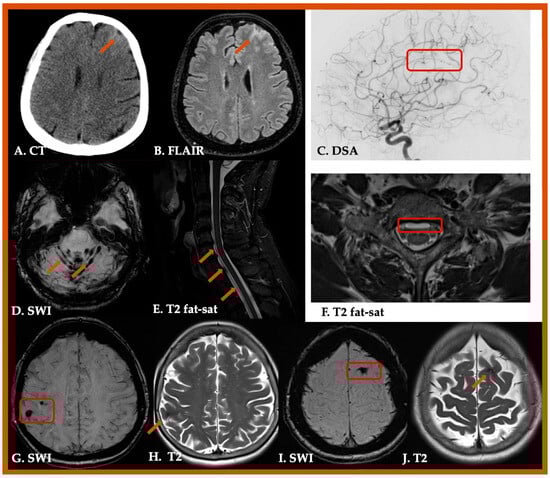

| 1. Definite CAA-ri | Definitive diagnosis of CAA-ri requires brain biopsy. |

| 2. Probable CAA-ri | 1. Age > 40 y 2. Presence of ≥1 of the following clinical features: headache, decrease in consciousness, behavioral change, or focal neurological signs and seizures; the presentation is not directly attributable to an acute ICH 3. MRI shows unifocal or multifocal WMH lesions (corticosubcortical or deep) that are asymmetric and extend to the immediately subcortical white matter; the asymmetry is not due to past ICH 4. Presence of ≥1 of the following corticosubcortical hemorrhagic lesions: cerebral macrobleed, cerebral microbleed, or cortical superficial siderosis 5. Absence of neoplastic, infectious, or other cause |

| 3. Possible CAA-ri | 1. Age ≥ 40 y 2. Presence of ≥1 of the following clinical features: headache, decrease in consciousness, behavioral change, or focal neurological signs and seizures; the presentation is not directly attributable to an acute ICH 3. MRI shows WMH lesions that extend to the immediately subcortical white matter 4. Presence of ≥1 of the following corticosubcortical hemorrhagic lesions: cerebral macrobleed, cerebral microbleed, or cortical superficial siderosis 5. Absence of neoplastic, infectious, or other cause |